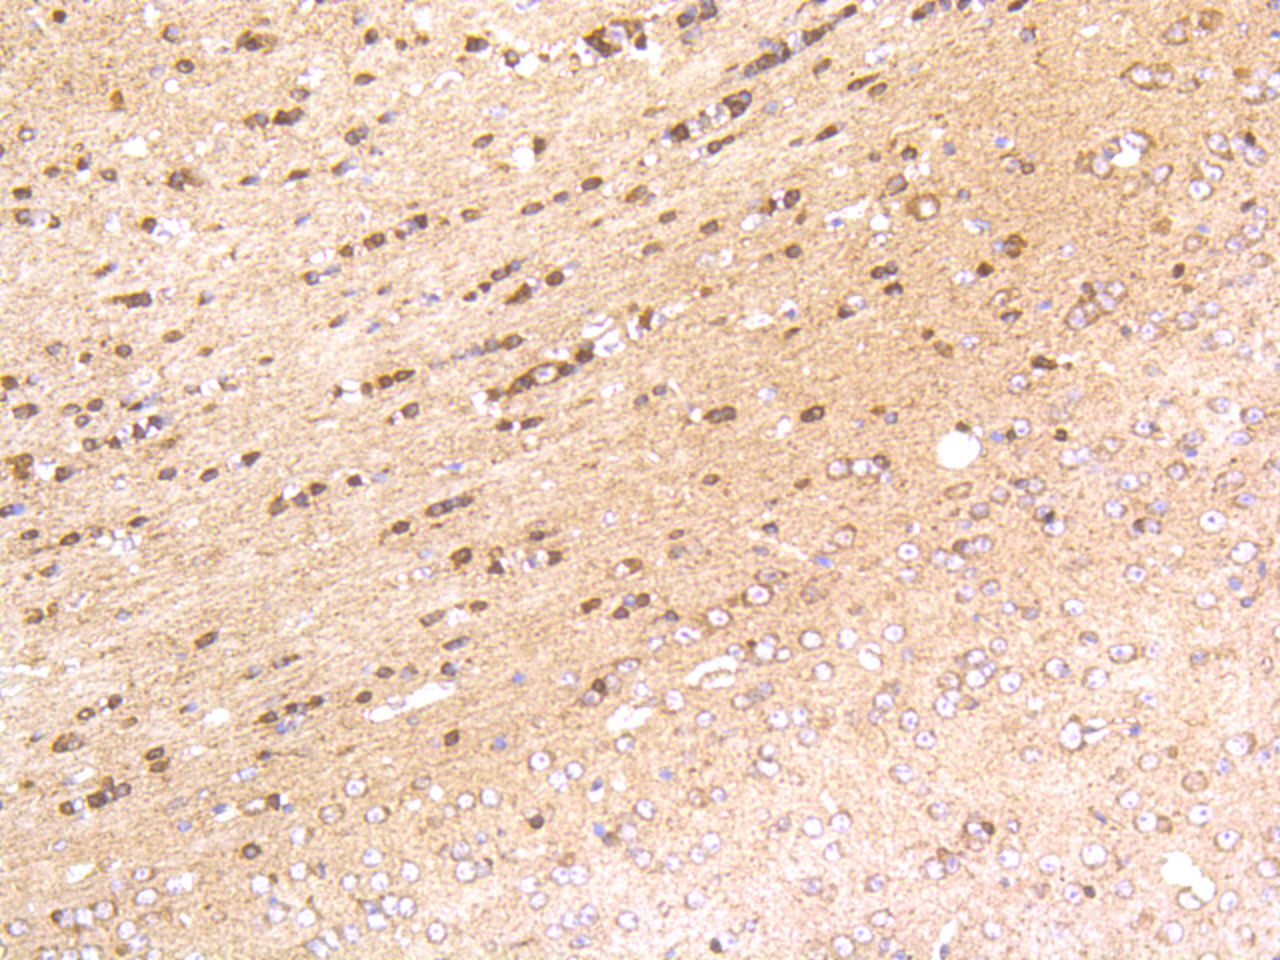

Immunohistochemical analysis of paraffin-embedded mouse brain tissue using anti- HSC70 antibody. Counter stained with hematoxylin.